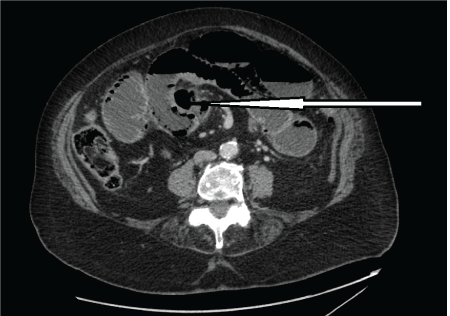

Figure 1: CT scan showing multiple jejunal diverticula and apparent air within the bowel wall. Large diverticula indicated by an arrow.

Figure 2: CT scan showing multiple jejunal diverticula mimicking pneumatosis intestinale. Multiple jejunal diverticula indicated by an arrow.

The differential diagnoses of acute small bowel obstruction and acute ischaemic bowel were entertained. An urgent CT scan of abdomen and pelvis showed a long segment of obstructed and possibly ischaemic dilated small bowel with pneumatosis intestinale (air within the bowel wall) (Figure 1 and Figure 2). There was an abrupt zone of transition at the junction of the proximal two thirds and distal one third of the small bowel. No free peritoneal air or fluid visualised. The patient and family were fully counselled on the risks and benefits of an emergency laparotomy, and given her fair premorbid state, decision was finally taken for emergency laparotomy. The findings at operation included a large obstructing enterolith within the proximal ileum, multiple jejunal diverticulae with three concealed perforated diverticulae walled off by bowel loops and omentum (Figure 3 and Figure 4). The whole of jejunum and proximal ileum were dilated and distal ileum was collapsed with cut off at the level of the impacted enterolith. There was also a near perforation at the level of enterolith impaction. The impacted enterolith was milked after a 40 cm segment of distal jejunum and proximal ileum involved with perforations were resected and a side-to-side TLC 75 stapled anastamosis was carried out. The histology of the resected specimen showed a 40 cm with perforations and evidence of peritonitis. There were focal mucosal ulcerations with abscess formation in small bowel at the sites of diverticular perforations.

A computed tomography (CT) scan is a useful modality for diagnosis but CT findings often do not correlate with the clinical picture in jejunal diverticulosis [4]. This patient is a typical example that can generate a great diagnostic confusion due to the CT scan. These multiple jejunal diverticulae were mistaken for pneumatosis intestinale which is a late radiological sign of acute ischaemic bowel with a significantly high associated morbidity and mortality. The point against acute ischaemic bowel in this patient was the fact that she looked unusually and relatively well for her age in spite of the presence of the acute abdomen. The diagnosis is often made at laparotomy in complicated jejunal diverticulosis and 8-30% of patients were previously noted to require surgical intervention in one study [6]. Diagnostic laparoscopy has been advocated in cases where symptomatology is complex and uncertain. This can be regarded as a diagnostic tool and preclude the need to proceeding to a full exploratory laparotomy [7].